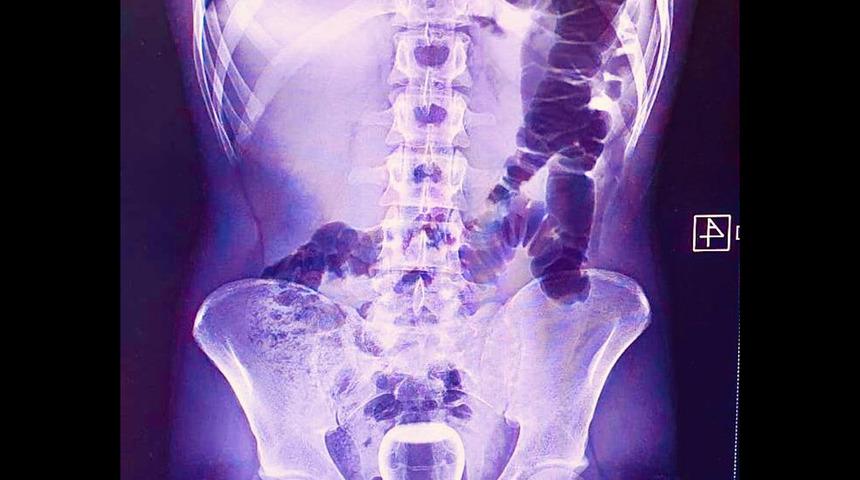

Geçen cuma günü ismi açıklanmayan bir kişi Mehmet Akif İnan Eğitim ve Araştırma Hastanesin'e başvurdu. Acil serviste hastanın çekilen röntgeninde anüs bölgesinde çay bardağı görüldü.

Şanlıurfa’da basur hastası olan bir kişinin iddiaya göre tedavi için hacamat yaptırırken yağlı çay bardağı anüs bölgesine kaçtı. Bardak ameliyatla çıkarıldı.